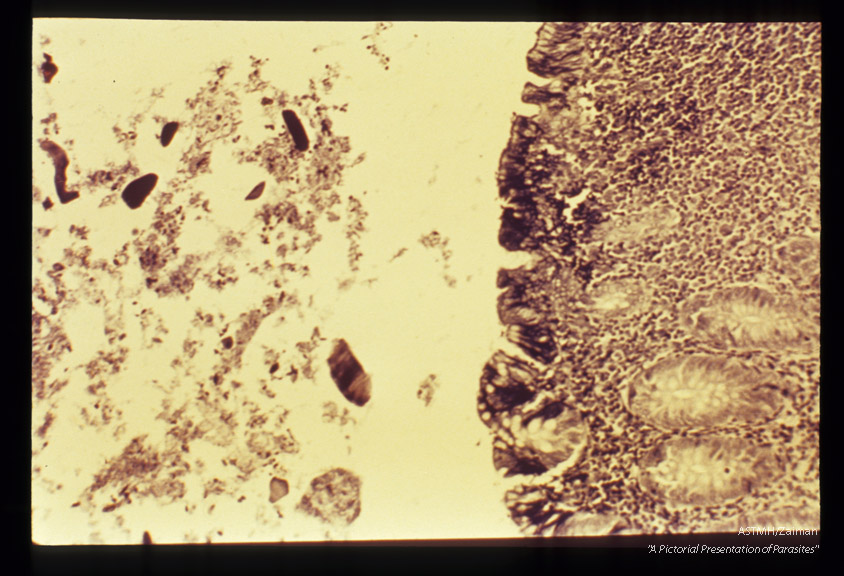

Human appendix, low and high powers. Iron hematoxylin stain.

Dientamoeba fragilis

Description: Human appendix, low and high powers. Iron hematoxylin stain.